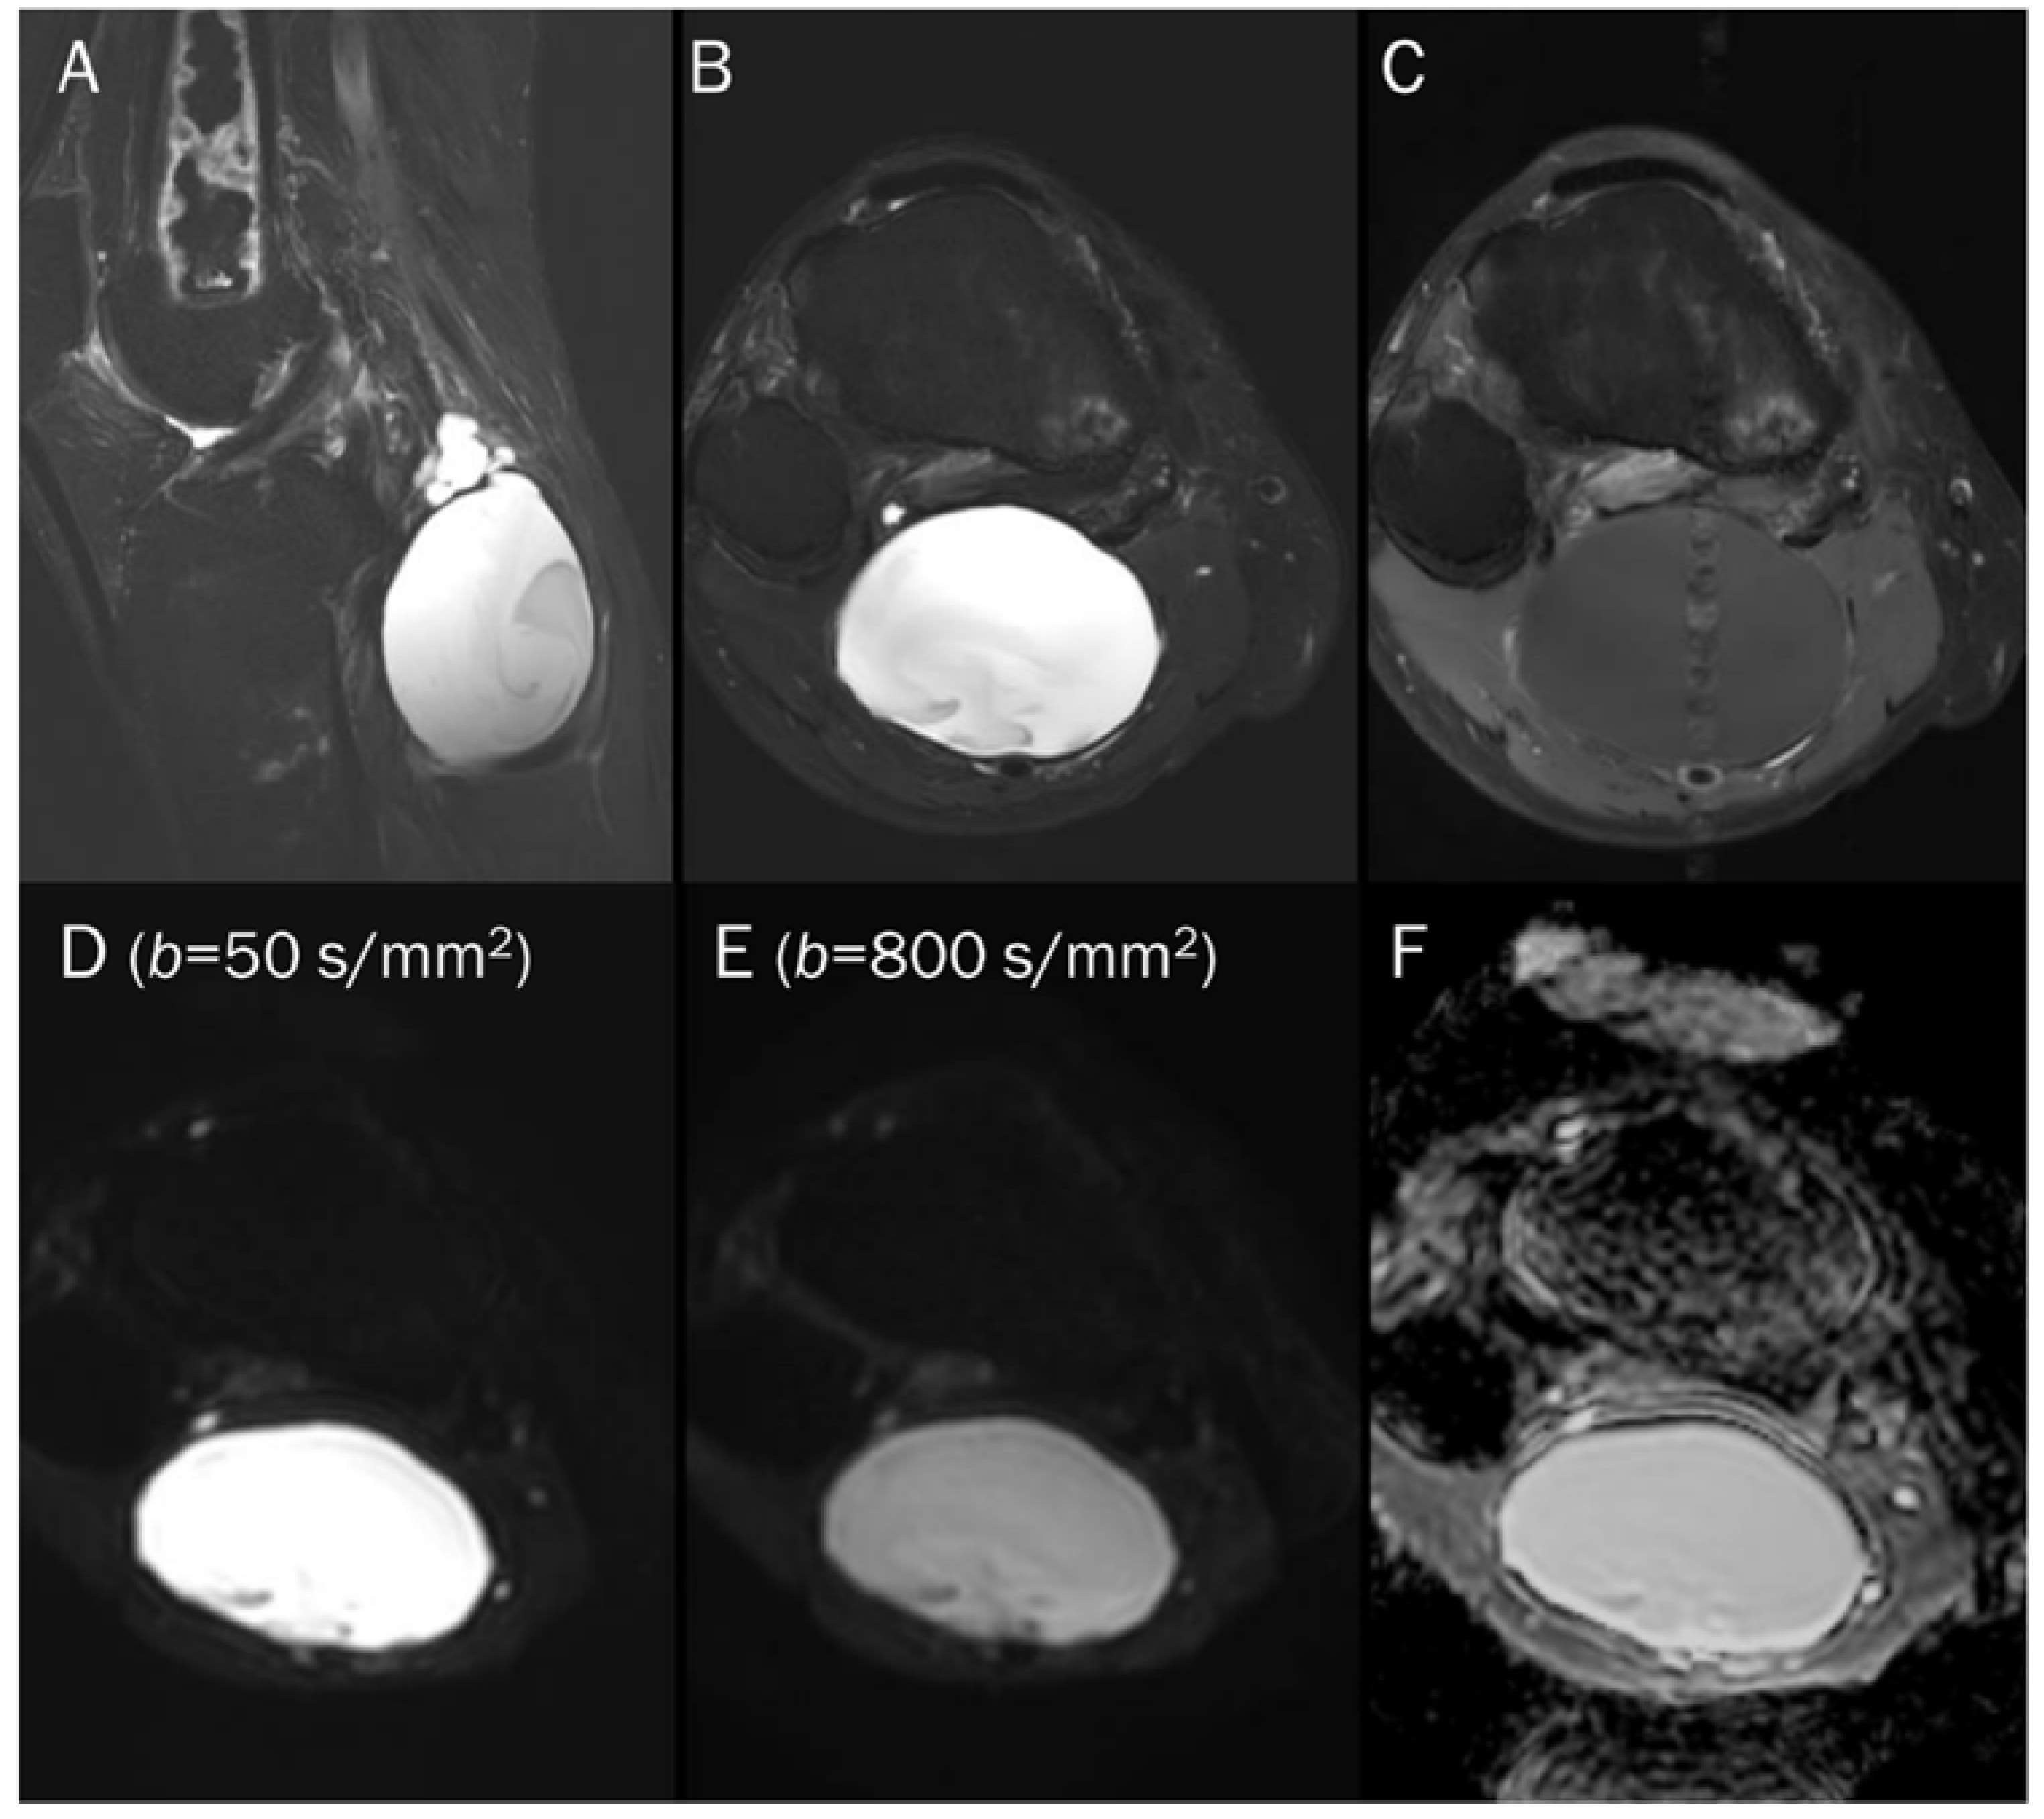

7.1. Cyst

| Benign cyst | T2 shine-through | Free water |

- Subhawong, T.K.; Durand, D.J.; Thawait, G.K.; Jacobs, M.A.; Fayad, L.M. Characterization of soft tissue masses: Can quantitative diffusion weighted imaging reliably distinguish cysts from solid masses? Skelet. Radiol. 2013, 42, 1583–1592. [Google Scholar] [CrossRef]